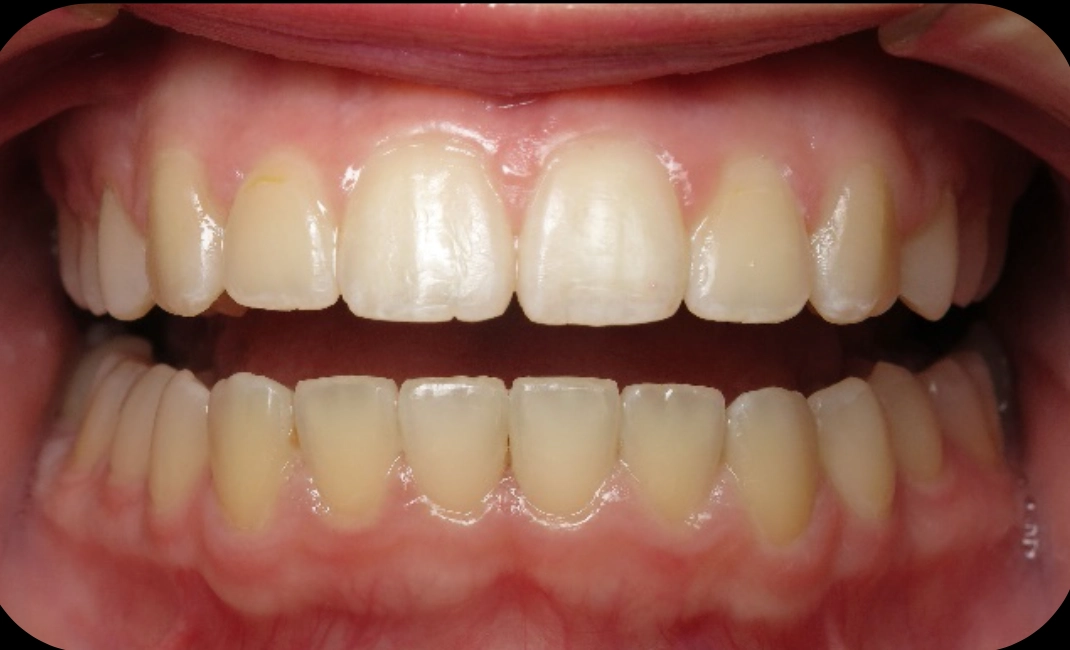

Patient treated with braces

Before

After